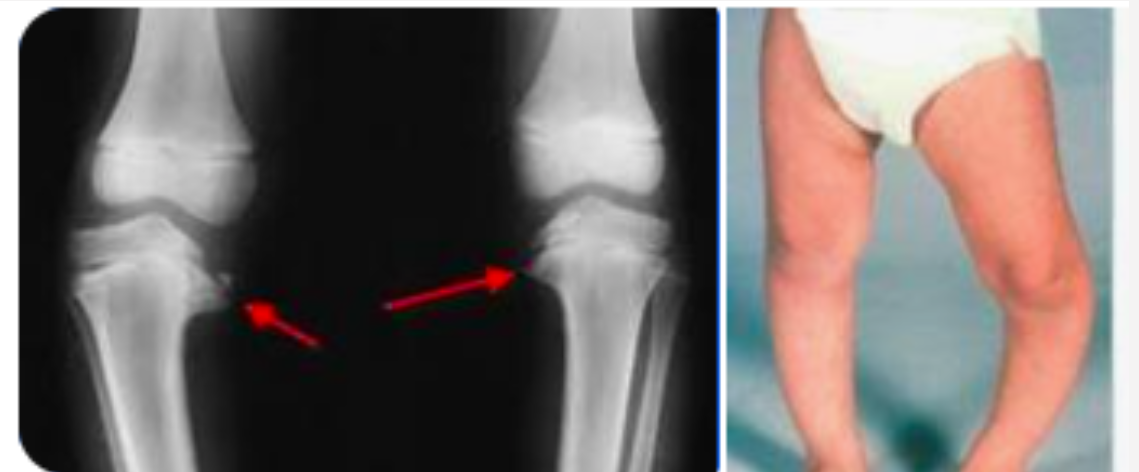

11

Q

This shows

osgood-schlatter

blounts disease

SUFE

Perthes

CDH

A